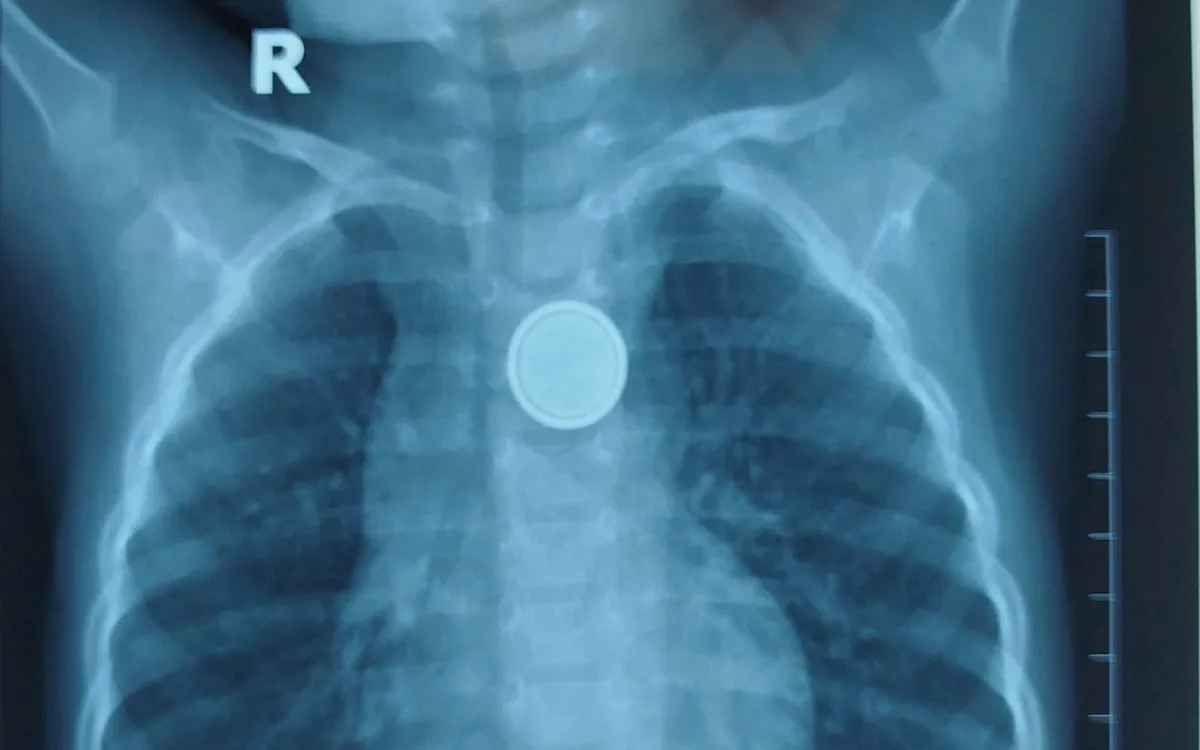

Kết quả X-quang cho thấy dị vật mắc lại ở thực quản. Các bác sĩ tiến hành nội soi cấp cứu và gắp thành công viên pin. Tuy nhiên, quan sát trực tiếp tại vị trí mắc cho thấy vùng thực quản đã bị ăn mòn và loét lớn - minh chứng pin cúc áo có thể gây tổn thương nặng nề chỉ trong thời gian rất ngắn, dù trẻ được đưa đến viện sớm.